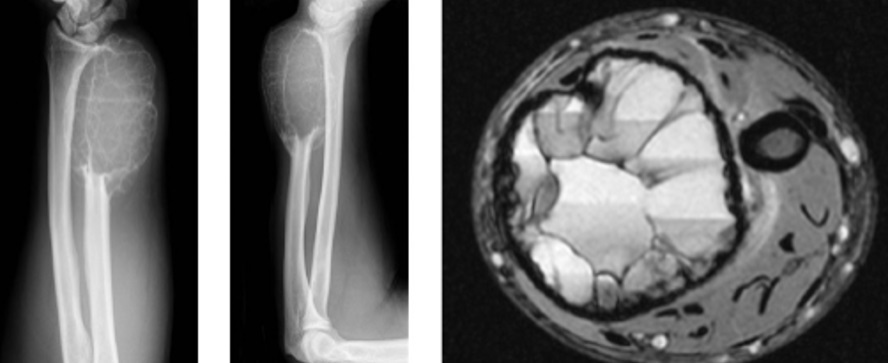

1

Q

Qual diagnóstico?

A

Lesão epifisária excêntrica

Fise aberta

dx: condroblastoma